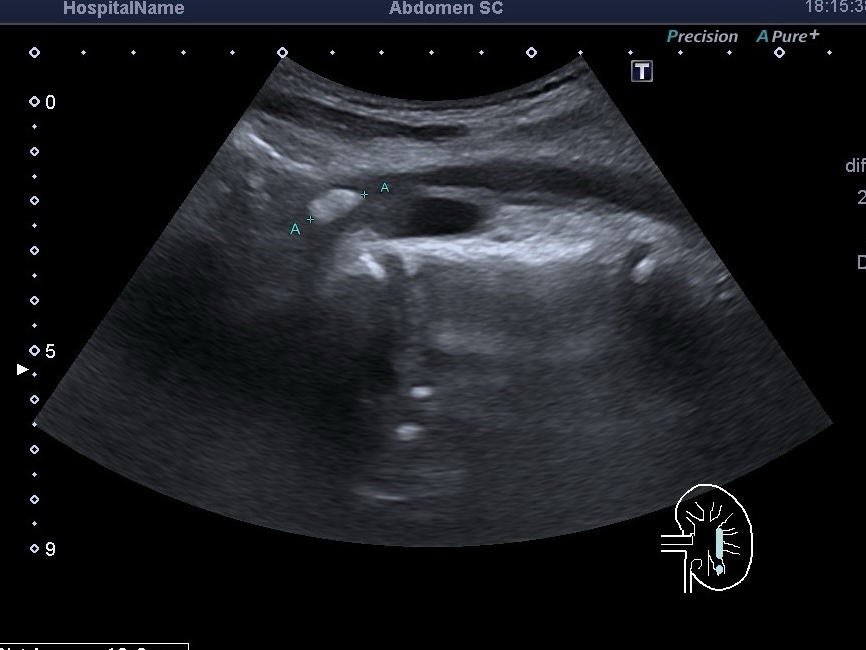

УЗД органів черевної порожнини при захворюваннях крові Під час ультразвукового дослідження (УЗД) органів черевної порожнини увагу звертають не лише на...

УЗД органів черевної порожнини, УЗД селезінки, спленоз Ультразвукова діагностика може виявити такі патології ,які змінюють життя пацієнта. Обов’язково перед обстеженням...